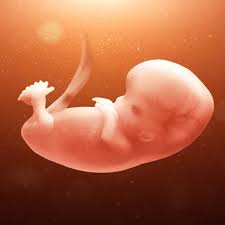

تطور نمو الجنين من الأسبوع التاسع وحتى الثاني عشر الجمال نت

تكو ن الجنين الأسبوع التاسع من الحمل بيبي سنتر آرابيا

تكو ن الجنين الأسبوع التاسع من الحمل أنا مامي

تكو ن الجنين الأسبوع التاسع من الحمل موسوعة